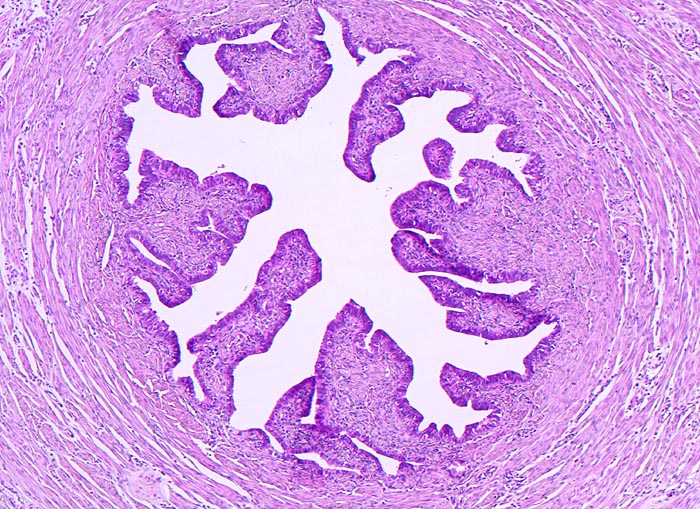

AP/ Tubargravidität

Tubargravidität

Tuba uterina